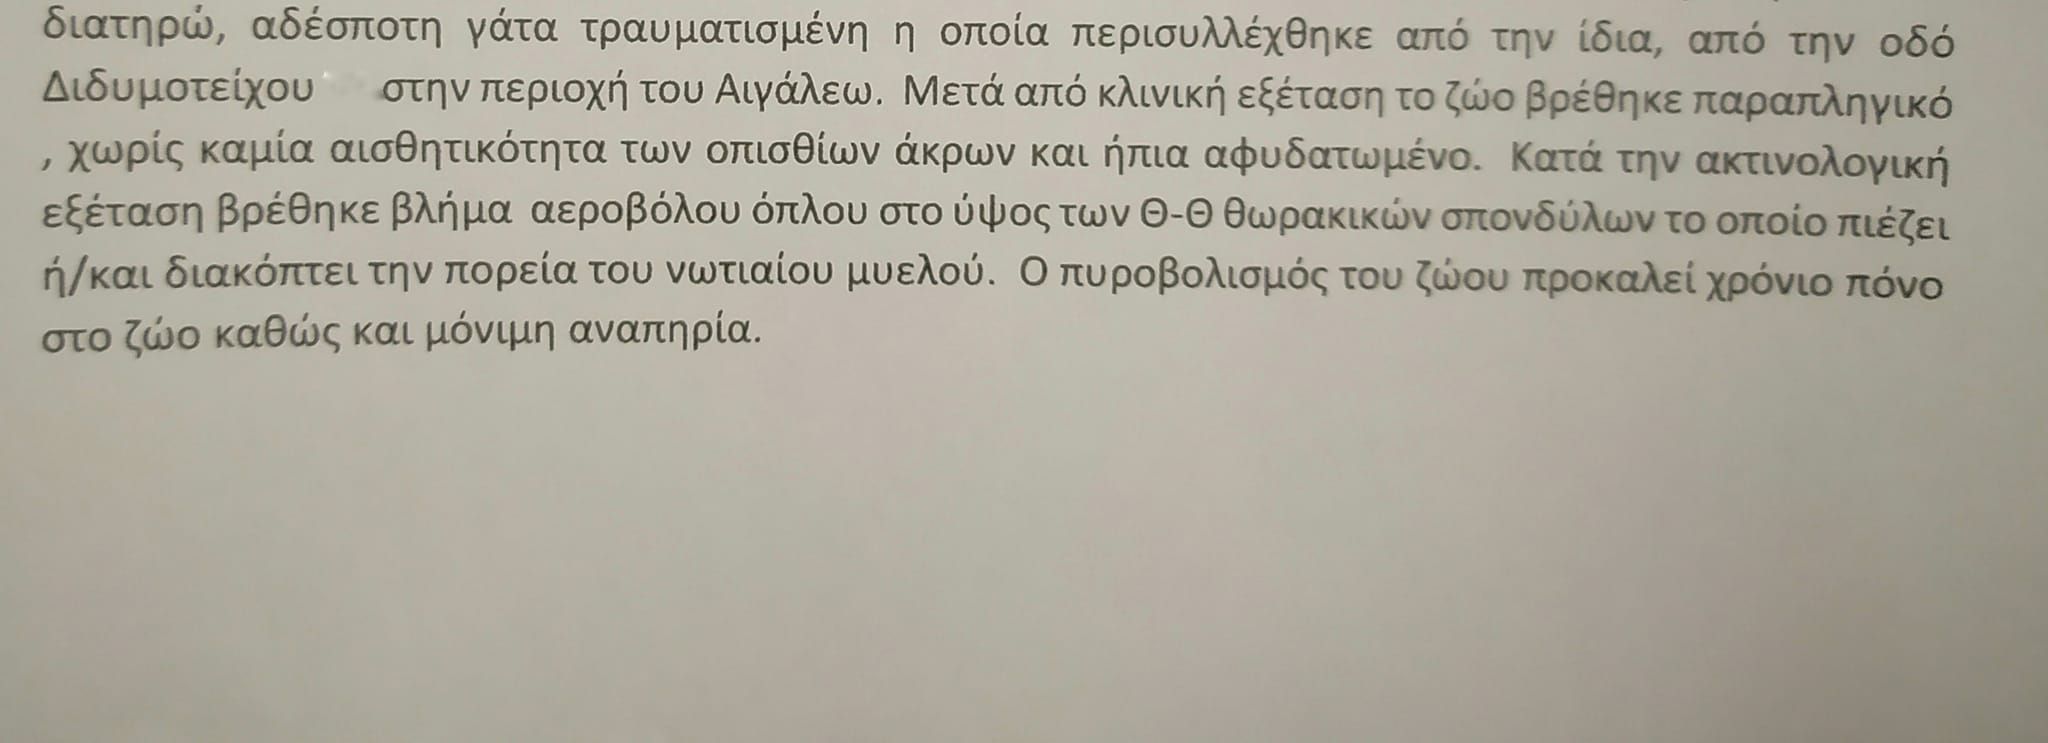

Η γνωμάτευση του κτηνιάτρου.

Η γνωμάτευση του κτηνιάτρου.